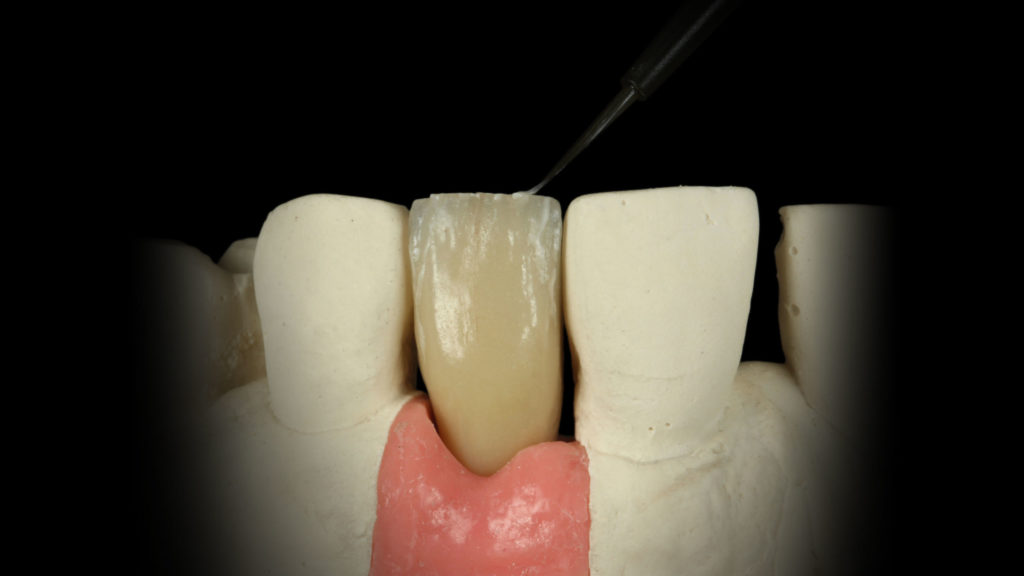

Vor dem internen Bemalen (Internal Live-Staining) wurde die Krone etwas in Form geschliffen und dann mit Glasurflüssigkeit befeuchtet. An dieser Stelle zogen wir nochmals die DSLR-Aufnahmen der Ausgangssituation und Nachbarzähne zurate, um relevante Charakteristika erkennen und entsprechend reproduzieren zu können (Abb. 22a bis c). Wir starteten das Internal Staining mit dem Anlegen von Sprüngen, die ausgehend von der Inzisalkante mit Weiß und Creme in Richtung Zentrum der Krone angelegt wurden (Abb. 23 bis 26). Vor dem Fixierbrand wurden die Malfarben noch schnell außerhalb des Ofenraums getrocknet. So wird sichergestellt, dass die Malfarben beim Brennen nicht verlaufen und sich die Position der aufgebrachten Effekte nicht verschiebt (Abb. 27). Da der zu rekonstruierende Zahn für diesen Fall unterschiedliche innere und äußere Merkmale aufwies und dennoch eine in sich geschlossene Einheit ergeben sollte, stellte sich die Schichtung als Herausforderung dar. Die Lösung bildete eine Kombination aus der Internal-Live-Staining-Technik von Meister Hitoshi Aoshima mit Universal Stain and Glaze (Dentsply Sirona) und einer dezidierten Schichtung – und zwar im tatsächlichen Wortsinn in unterschiedlichen Schichten. Denn damit die Technik des Internal Stainings richtig zur Geltung kommt, ist es wichtig, eine korrekte, farbgebende Basis aus Dentin und Schmelz zu schaffen. So, wie wir es in Form des Grundkörpers getan hatten.

Auf den mittels Internal Staining charakterisierten Grundkörper wurde nun mit Dentin Opaque B4 der freiliegende Wurzelbereich akzentuiert. Im zervikalen und mittleren Drittel wurde eine 1:1-Mischung aus Dentin A3,5 und Enamel Clear aufgetragen und ebenfalls mit einer 1:1-Mischung Enamel Light und Enamel Clear das inzisale Drittel vervollständigt. Enamel Extra Light, das an den Rändern aufgetragen wurde, schloss die Schichtung ab (Abb. 28a und b). In den Abbildungen 28c ist der gebrannte Grundkörper der Implantatkrone zu sehen. Dieser Zwischenschritt war somit abgeschlossen. Würden wir Begriffe aus dem Wortschatz eines Visagisten verwenden, dann könnte man diesen Schritt als Foundation-Auftrag bezeichnen. Auf diese Grundierung, die aber auch schon Farbinformationen und Charakteristika aus der Tiefe beinhaltet, wird nun das Make-up aufgetragen.

Der abschließende Auftrag von Verblendkeramik ist eher kosmetischer Natur und kann als Make-up betrachtet werden. Dieser Schritt ist dennoch sehr wertvoll und hilft uns, einen Tiefeneffekt zu erzielen (die in der darunterliegenden Schicht befindlichen Informationen an die Oberfläche zu bringen) und der Restauration seine endgültige Form zu geben (Abb. 29a bis 29c). Entsprechend unserer Beobachtungen und Analysen, der Patientendaten, der Morphologie und der Textur, die wir am Arbeitsmodell ablesen konnten, waren wir nun in der Lage, all diese Merkmale gezielt kopieren und auf unsere Restauration anwenden zu können.